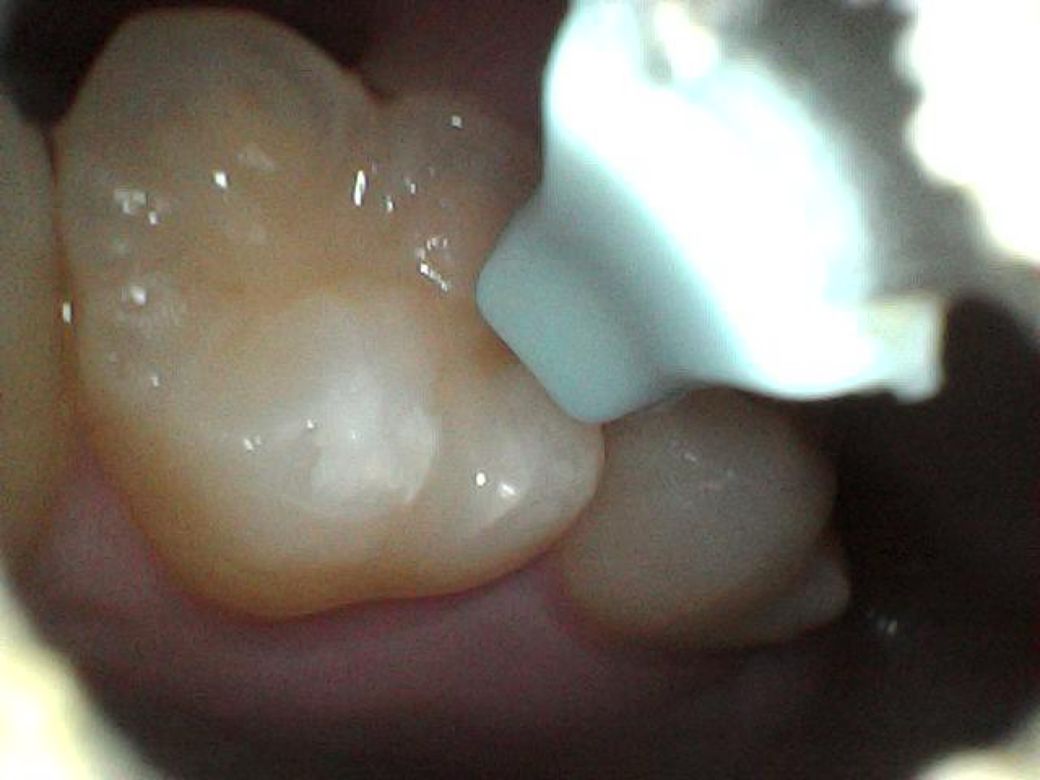

어제 아침, 오늘 아침 이틀동안 찍은 사진들인데 이거 혹시 사진으로 뭔지 구분이 가능할까요?

처음 두장이 어제, 나머지가 오늘 사진입니다

오늘

특별히 무엇이 보이지는 않습니다. 크기가 줄어든 것으로 보인다면 충치보다는 치석일것 같습니다.

사진만으로 정확히 파악은 어려우나, 현재 초기 충치단계로 보이기에 빠른시일내에 치과에 방문하여 상태를 확인하고 치료를 받길 권합니다.

치석의 형상은 아니고 초기충치 내지는 이전에 떼운재료가 떨어지거나 마모된 것 같습니다 치료가 시급한 정도로의 충치는 아닌것 같습니다